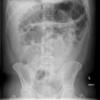

AXR: sentinel loop, pancreatic calcification